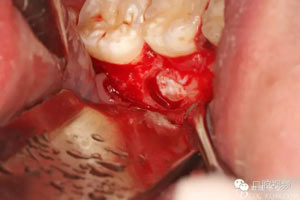

圖9.分牙、分別取出牙冠和牙根

圖11.清理拔牙創(chuàng)。

圖12.取出是埋伏牙牙根